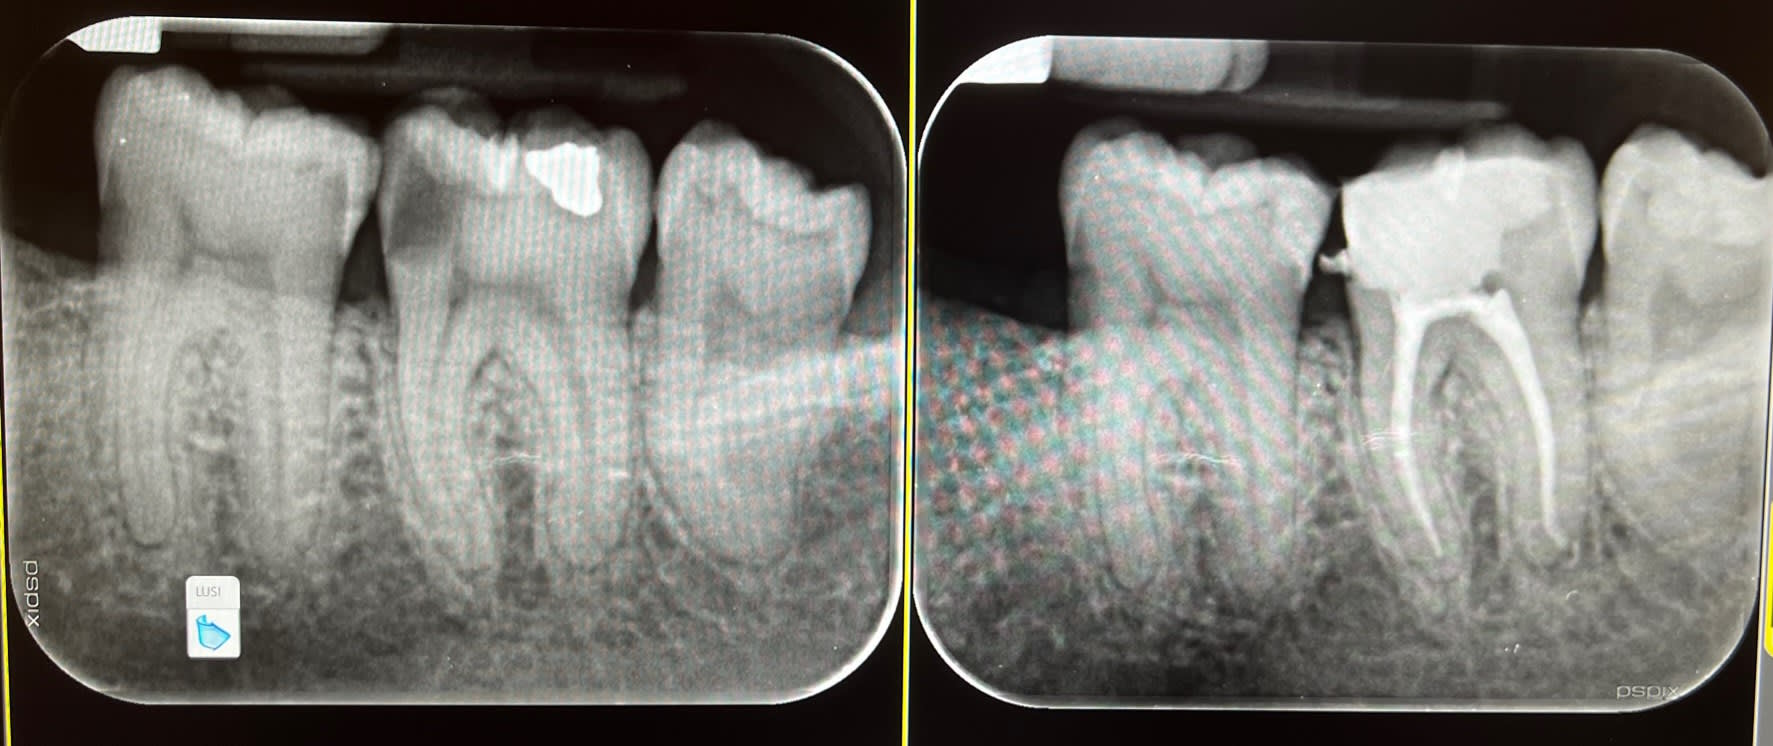

Je couronne pas toutes les dents dépulpées que je vois , si il y en a le besoin je reprends l'endo quand j'ai une image à l'apex , autrement je le fais pas si radiographiquement tout va bien. Et pour ce qui est du spé endo bah écoute le plus proche il est à 200km de mon cabinet donc comment te dire qu'on fais en sorte de pas en avoir besoin.

Mes endos sont sous digue, peut être pas digne d'un spé endo mais j'en suis satisfait

C'est juste du travail normal et un cas simple quelques endos et couronnes. Ca n'a rien d'un plan de tt global multi disciplinaire. ( ortho, paro occluso.....)

1 : elles sont toutes déjà pratiquement toutes couronnées. sinon je laisse

2; j'ai arrêté quand je ne les trouve pas il ne les trouve pas non plus. -)